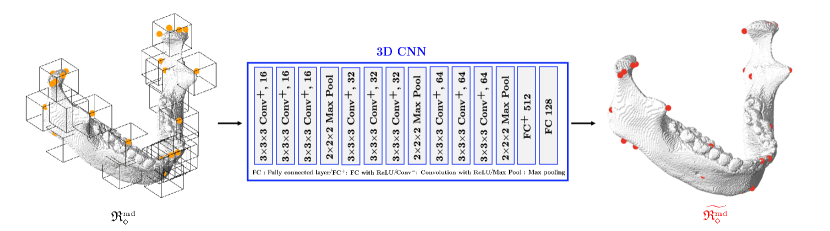

For landmarks on the mandible being articulated to the skull, a patch-based 3D CNN is applied to capture the morphological variability of the 3D mandibular surface geometry associated with the landmarks. Let be a roughly estimated position of a landmark with index in . See A for details of the landmark index. For each mandibular landmark (i.e., ), we extract a 3D image patch , which is defined by a cube whose edge length is and center is . By using 3D CNN, we obtain a map , where is an accurate positional estimation for the landmark with index (i.e., ).

To learn the fine detection map , we generate a training dataset by using the paired dataset as follows. For a given index , 3D patches with edge lengths of are extracted from by varying the center location of patch in basis of label landmark position . As a result, the following dataset is obtained.

where and is the maximum length of the center position variation. Using this dataset, the 3D CNN is trained as follows:

where is a class of functions in the form of a 3D CNN. As seen in Figure 4, the 3D CNN is used that possesses an architecture modified from VGGNet [Simonyan2014].

In practice, several landmarks are identified in a group at once. We simultaneously identify six landmarks on the condyle (COR, MCP, LCP, Cp, Ct-in, and Ct-out), which are positionally related to one another, as well as landmarks with bilaterality (e.g. left/right mandibular foramen), which are associated with the symmetric structure of the mandible. For this group detection, we construct a 3D CNN to produce a concatenated vector of all landmark positions on the same group from one 3D image patch.

For fine detection of the mandibular landmarks, 3D image patches were extracted with size of voxels (). To generate the training data in (11), the center location of patch was varied to cover 2 times the maximum error of the initial estimation of for the training data. Using the parameters of 20000 epochs, a full batch size, and a 0.0001 learning rate, nine 3D CNNs were trained.

Figures 7(b) and 8(b) show the qualitative and quantitative results of the 3D CNNs. The mean 3D distance error decreased to 2.72 mm when compared to the initial detection error of 4.23 mm (Figure 6(b)). According to results shown in Table 3, the proposed method achieved an error range of 1 to 4 mm for the detection of most landmarks. In addition, as shown in Figure 10(b), the proposed method significantly reduced the mean and variance of error for the test subjects, compared to the initial detection.